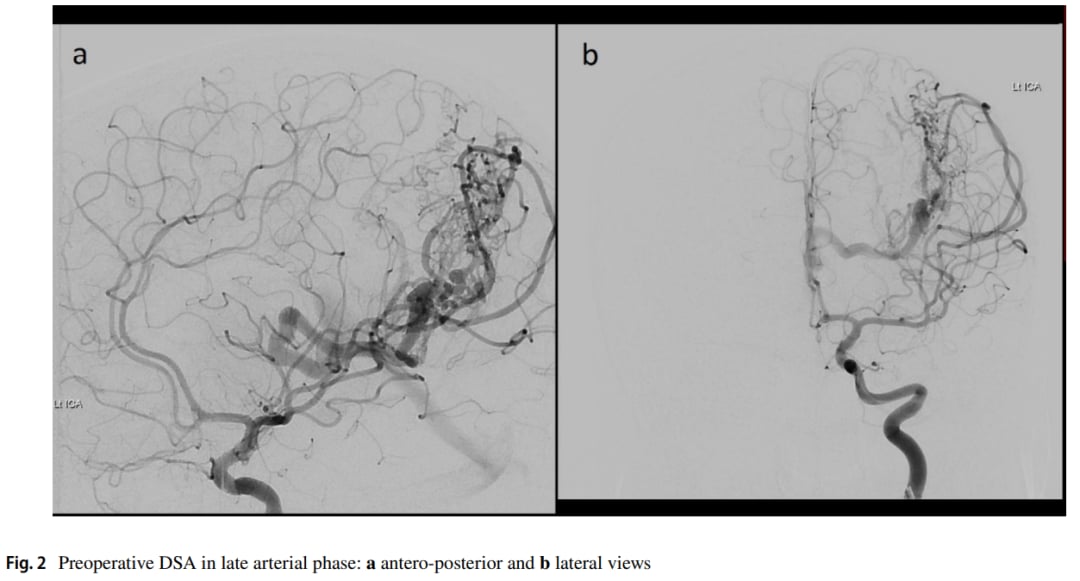

▲图1 术前轴向MRI影像

本文首次详细报道了一例大型AVM与分子定义的乳头状胶质神经元肿瘤(PGNT)在空间和时间上共存的病例。一名10岁女童因持续头痛和恶心就诊,MRI检查显示左侧顶叶存在病变,并伴有明显的血管异常。数字减影血管造影(DSA)进一步证实了高流量动静脉畸形的存在。在遵循AVM手术原则成功切除病变后,组织病理学和基因测序结果令人瞩目。

病理分析显示,肿瘤由相对单一形态的小上皮样细胞组成,具有血管周围假菊形团结构。更关键的是,全基因组测序检测到了SLC44A1::PRKCA融合,这正是乳头状胶质神经元肿瘤的特征性分子改变。这一发现不仅确诊了肿瘤类型,也为理解其与AVM的共存提供了分子层面的线索。